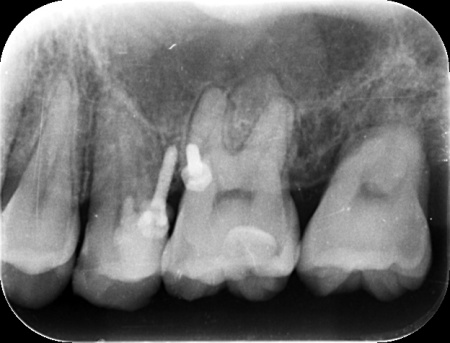

拝見したところ、左上奥歯(第2大臼歯)には被せ物が装着されていましたが、その下で虫歯が再発しており、歯の温存が難しい状態でした。

抜歯後の治療方法には、顎の骨に人工歯根を埋め込むインプラントなどがありますが、患者様の年齢が若いことを考慮して、抜歯部位の後ろに埋まっている親知らずを利用する方法を検討しました。

親知らずを一度抜いてから移植する方法もありますが、これでは歯の神経を失います。

そのため、治療期間は長くなるものの、歯の寿命を延ばすためにも矯正治療で親知らずを抜歯部位まで移動させる方法を提案し、こちらも同意いただきました。